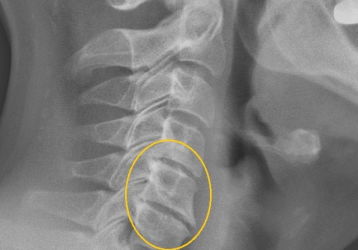

Боль в горле при шейном остеохондрозе: как диагностировать, чем лечить

Может ли возникать боль в горле при шейном остеохондрозе: основные причины болевого синдрома, способы диагностики, основные методы лечения.